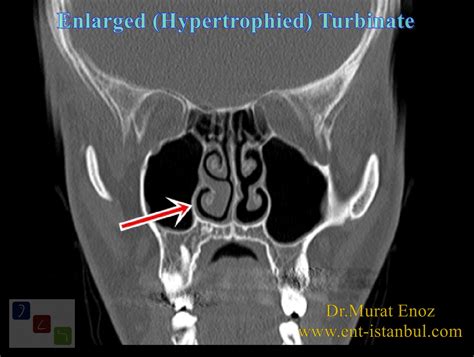

- CT Scan: In cases where surgery might be necessary, a CT scan provides a detailed view of the bony structures and the soft tissue to determine if the hypertrophy is mucosal or bony in origin.

| Size | Slim, allowing clear airway | Bulky, filling the nasal cavity |

| Mucosa | Smooth and thin | Swollen, edematous, or textured |

| Airflow | Clear and unobstructed | Severely restricted or blocked |